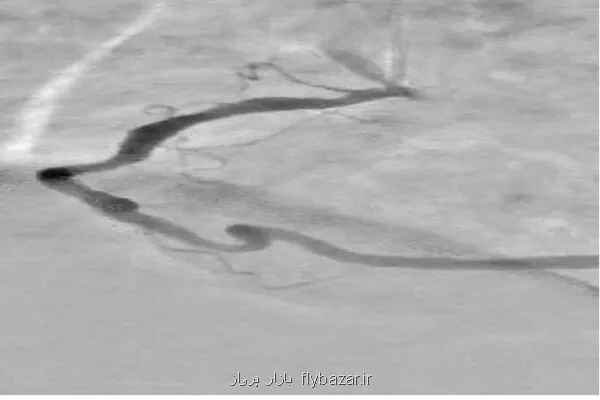

آخوندی با اشاره به علل انتخاب این پژوهش، توضیح داد: در آنژیوگرافی قلب، تداخل سایه های ناشی از بافت ها و استخوان های قفسه سینه و همین طور حرکات تنفسی و ضربان قلب سبب می شود تشخیص دقیق عروق کرونری دشوار شود. این مسئله منجر به نیاز به تزریق بیشتر ماده حاجب و دریافت دوز بالاتر اشعه توسط بیمار می شود.

وی بخش نوآورانه طرح را شامل استفاده از شبکه خودرمزگذار هدایت شده برای بازسازی پس زمینه تصاویر حاوی ماده حاجب از تصاویر بدون ماده حاجب ذکر کرد و اضافه کرد: همین طور در طراحی شبکه های عصبی عمیق متناسب بودن با تصاویر آنژیوگرافی به سبب مقیاس خاکستری آنها و ظرافت عروق در طراحی لحاظ شده است.

آخوندی خاصیت های این طرح را شامل افزایش وضوح عروق کرونری در تصاویر آنژیوگرافی، کاهش نیاز به تزریق مقدار زیاد ماده حاجب و بنابراین کاهش خطرات در رابطه با آن برای بیمار دانست و اضافه کرد: همین طور نسبت به شیوه های سنتی، زمان پردازش تصاویر را بطور قابل توجهی می کاهد و می تواند حتی با در اختیار داشتن یک تصویر تکی حاوی ماده حاجب هم عمل اصلاح و پردازش را انجام دهد. سرانجام، استفاده از فناوری شبکه های عصبی عمیق، امکان استخراج و بازسازی هوشمند پس زمینه و جداسازی بهتر عروق را فراهم می آورد و طرح را از نظر علمی و کاربردی در سطح شیوه های نوین پردازش تصویر پزشکی قرار می دهد.